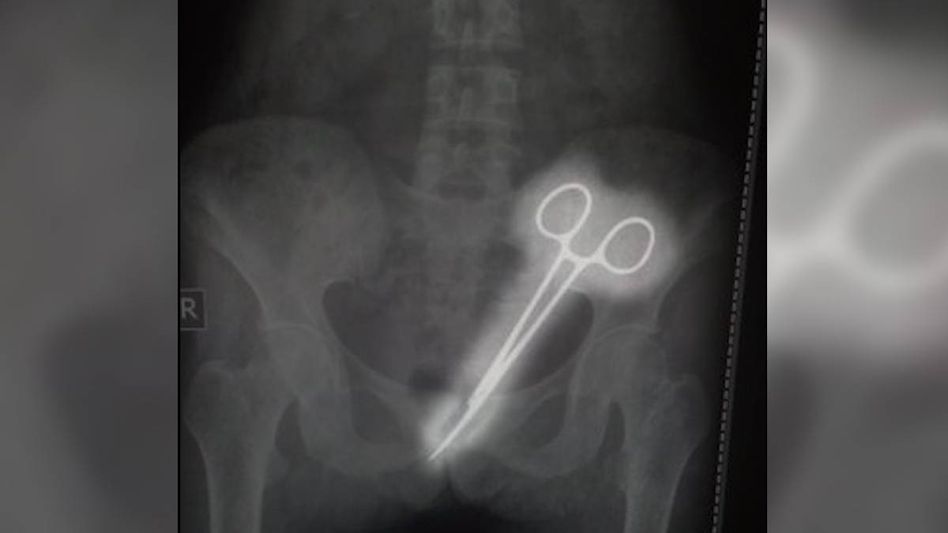

SIR Thutob Namgyal Memorial (STNM) Hospital is under fire for alleged medical negligence after a pair of surgical forceps was found in the abdomen of a woman 12 years after her appendix operation.

Years passed with no clear diagnosis until this year when Rita began experiencing urinary issues. After a biopsy in Namchi revealed concerning results, she was referred back to STNM for further examination. On October 7, doctors noted an infection, and an X-ray revealed the shocking discovery of the forceps.

Following the surgery, the hospital confirmed that the forceps were successfully extracted from Rita's abdomen.